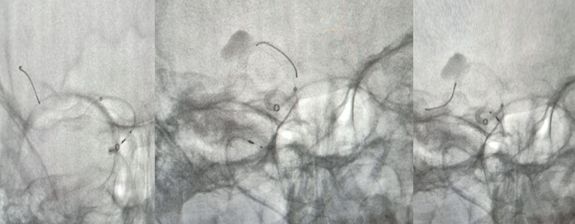

1、造影后显示右侧大脑中动脉M1段动脉瘤,路径图引导下由Traxcess(0.014,200 cm)微导丝携带Marksman支架微导管超选进入右侧大脑中动脉M2段远端(图一)。

2、Pipeline密网支架释放过程,图像显示支架打开及贴壁良好(图二)。

3、术后支架显影(图三)。

术前讨论:如何使患者获得最大受益?因为是夹层动脉瘤,如果填圈治疗,一是外侧豆纹动脉会即刻闭塞,更易引起临床症状;二是填圈治疗有使夹层动脉瘤撕开、出血的风险。所以经讨论我们决定采取一种折中方案,只放密网支架而不填圈的手术方式。我们希望通过密网支架的支撑,使夹层动脉瘤慢慢消失。通过慢性闭塞,给夹层动脉瘤上方的豆纹动脉部位一个代偿血管增生的时间,减少患者发生偏瘫的概率。经过精准测量后,选择合适支架。术中手术顺利,术后进行血管三维重建,密网支架放置良好,贴壁良好,可以清晰的看到豆纹动脉。术后患者回到病房后,一般情况良好。术后18小时后患者出现言语含糊、左侧中枢性面舌瘫,左侧肢体偏瘫,CT排查出血后考虑是患者夹层动脉瘤上方的豆纹动脉闭塞引起的症状。立即行全脑血管造影,发现豆纹动脉确实消失。确定豆纹动脉消失是引起患者临床症状的一个主要原因。这是天坛医院第一例在密网支架植入术后第一天就复查造影的患者。造影结果让我们惊喜的发现,密网支架治疗后,不到18个小时,患者的动脉瘤几乎完全消失。从而证明,我们的手术通过精准测量,选择合适的密网支架对夹层动脉瘤的治疗效果以及夹层的修复效果是非常明显的。当然,患者出现穿支动脉的闭塞,是我们术前充分考虑的,且无法避免的一个并发症。术后给予神经康复,高压氧治疗,患者有明显的好转趋势。我们希望通过后续的康复治疗可以使患者的生活接近正常,同时我们也在密切随访患者,希望患者动脉瘤完全消失,并且正常生活。